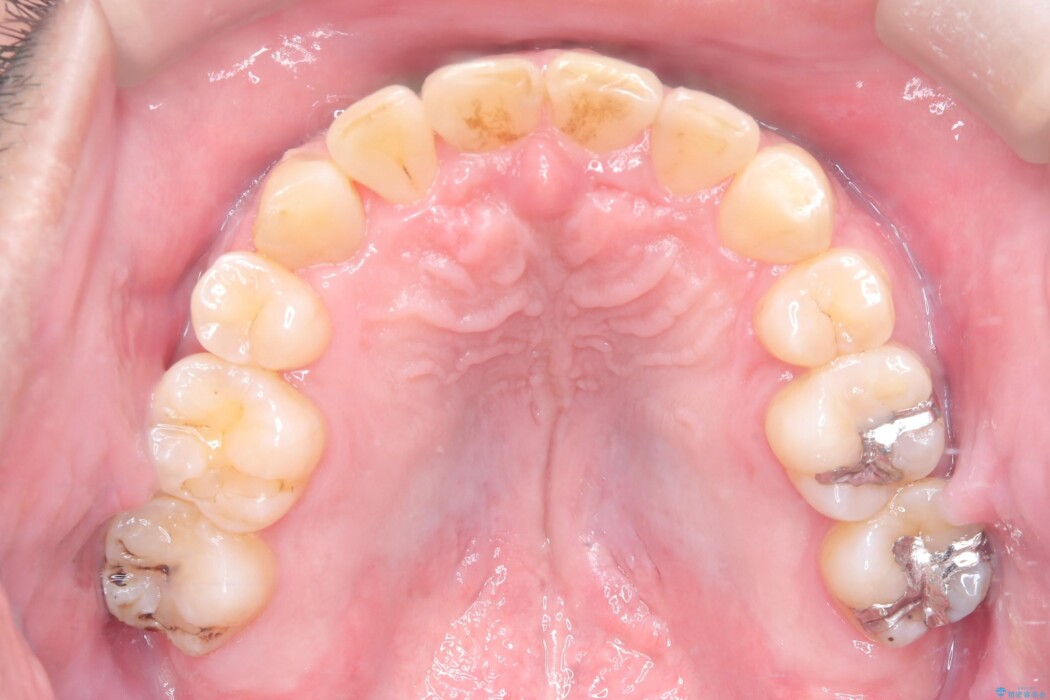

反対になっている嚙み合わせを改善したいとご来院されました。

診査の結果、上下左右4番の歯を抜歯し、審美装置にて反対咬合と叢生を改善していくこととしました。

骨格性Ⅲ級を示しましたが、構成咬合位がとれたことから反対咬合と叢生改善のため、上下左右第一小臼歯を抜歯しワイヤー矯正を行いました。途中、バイトアップを行っています。